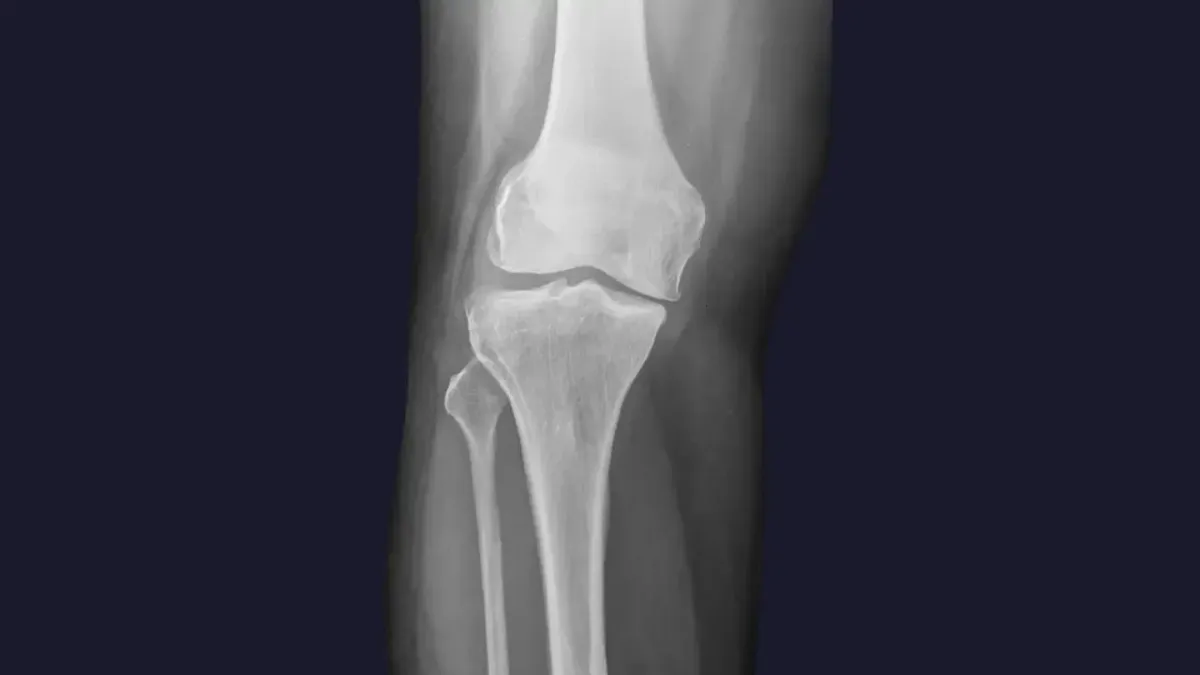

Knee pain is a widespread complaint, often stemming from a variety of sources. Here are some of the common culprits we see in Fort Mill :

Misalignment: Even subtle misalignments in the knee joint itself, or in the hips and pelvis, can lead to improper tracking of the kneecap, increased wear and tear, and pain.

Arthritis: Degenerative changes in the knee joint can cause stiffness, swelling, and chronic pain.

Ligament or Meniscus Issues: While severe tears may require surgical intervention, chiropractic care can help manage pain and improve function for less severe injuries by optimizing joint mechanics and supporting the healing process.

Poor Biomechanics: Imbalances in the muscles surrounding the knee, or issues with foot mechanics, can place excessive stress on the joint.